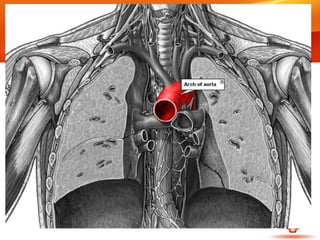

Arteria carótida primitiva izquierda

• Origen en el cayado aórtico, por

detrás del tronco braquiocefálico

• Asciende luego hacia arriba y afuera